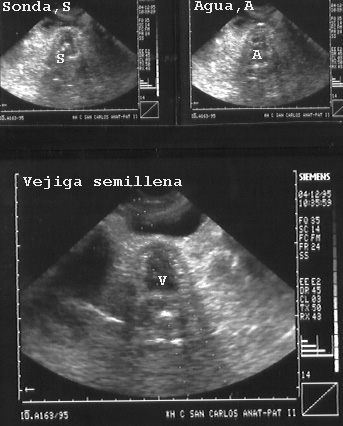

Cuando la vejiga esta vacía podemos llenarla con agua que se introduce por una sonda vesical. La Fig 34 es una composición de tres momentos: en el primero se visualiza la sonda, en el siguiente se empieza a ver entrar el agua y abajo ya está casi rellena la vejiga.

El sondaje vesical es muy fácil porque en el cadáver hay relajación de los esfínteres.